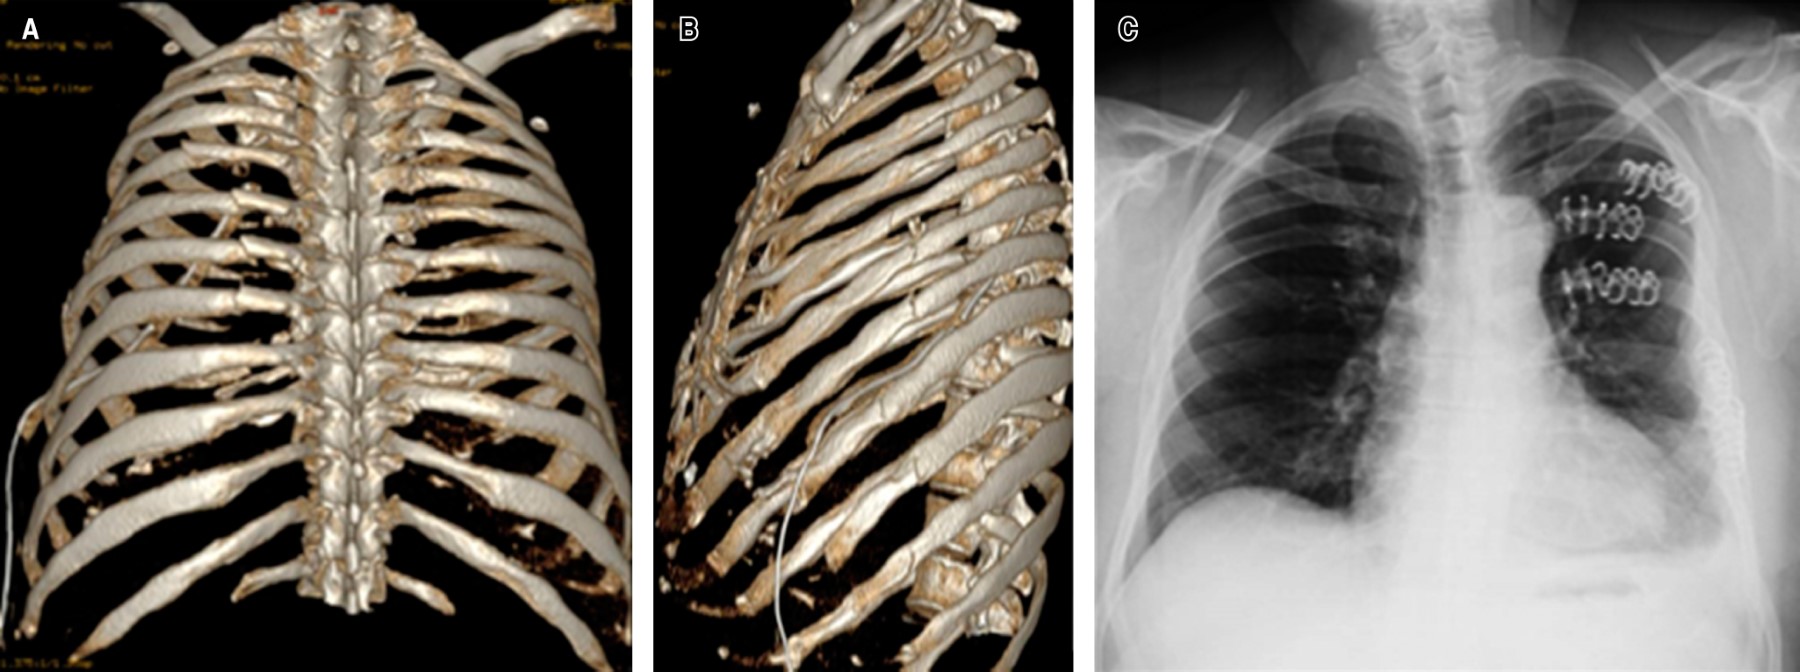

• ? Caso 3: masculino de 58 años de edad con luxación costocondral izquierdas (5-7), las cuales se fijaron con sistema StraCos® para los trazos simples y para el séptimo cartílago se utilizó un montaje de sistema StraCos® con sistema Tritium® para fijar el cartílago común al esternón (Figura 3).

Figura 3